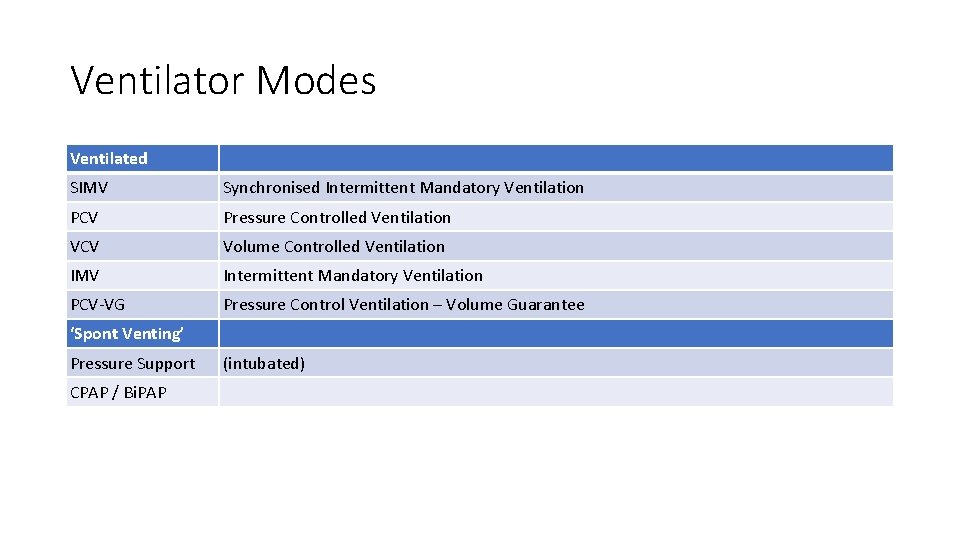

Ventilator Modes Ventilated SIMV Synchronised Intermittent Mandatory Ventilation PCV Pressure Controlled Ventilation VCV Volume Controlled Ventilation IMV Intermittent Mandatory Ventilation PCV-VG Pressure Control Ventilation – Volume Guarantee ‘Spont Venting’ Pressure Support CPAP / Bi. PAP (intubated)